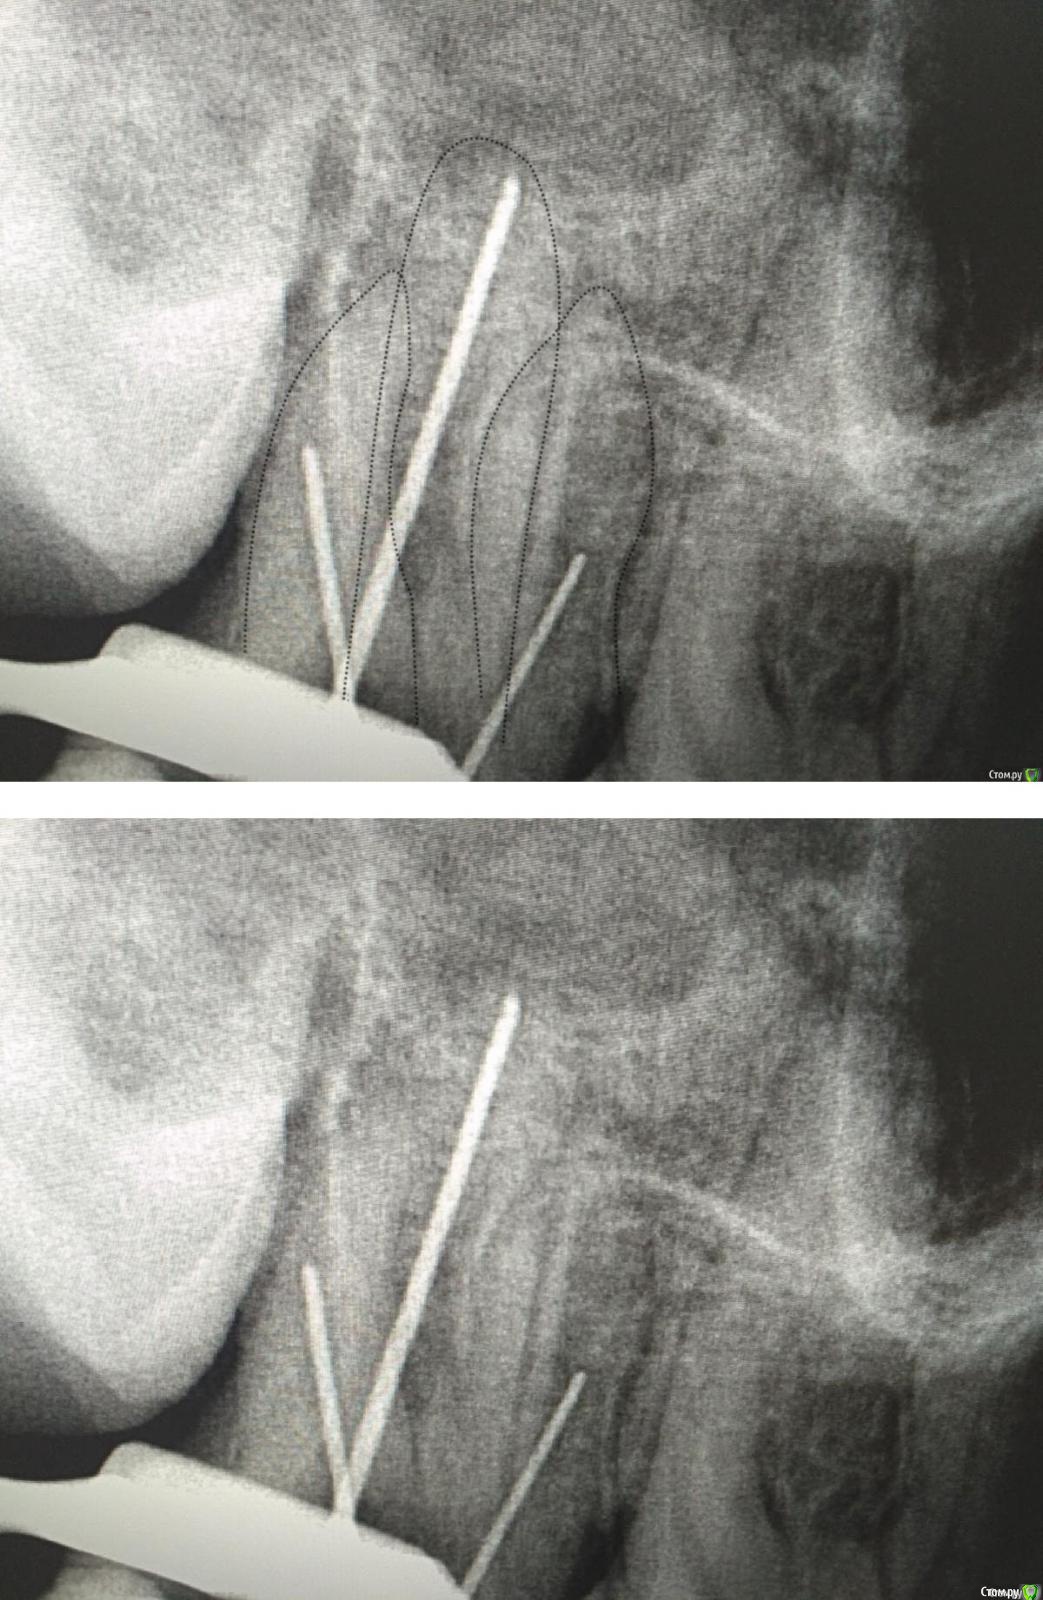

Romanson Опубликовано 9 января, 2017 Поделиться Опубликовано 9 января, 2017 (изменено) Снимок не очень информативный, мне почему-то видятся такие контуры корней.Я бы попробовал ещё раз CaOH2, если боли продолжаются, то на КТ, для определения точной локализации каналов. Изменено 9 января, 2017 пользователем Romanson Ссылка на комментарий

St. Опубликовано 9 января, 2017 Поделиться Опубликовано 9 января, 2017 Мне медиальный как и Вам видеться, с небные вопросов нет, дистальный неясно.Почему апекс орет на половине канала? Ссылка на комментарий

Romanson Опубликовано 9 января, 2017 Поделиться Опубликовано 9 января, 2017 Я просто ни разу не детский доктор, поэтому паникую слегка..Я тоже не детский )Сегодня делал эндо нижней 6ки, витальный случай, под конец мех/мед обработки, перед высушиванием каналов, почему-то очень захотелось взять H-файл и ещё раз пошкрябать и помыть. Взял, пошкрябал, из дистального достал кусок нерва где-то 1 на 1 мм Насколько я понял полноценную механическую обработку вы не делали, поэтому я бы смотрел в сторону остатков органики. Это объяснило бы боль и неточные показания ап.лока.Т.к. пациент молодой, возможно имеет место случай неокончательного формирования доп. каналов, т.е. я имею ввиду те случаи, когда лет через 5 это был бы отдельный канал, а сейчас это разные устья одного широкого. Ссылка на комментарий